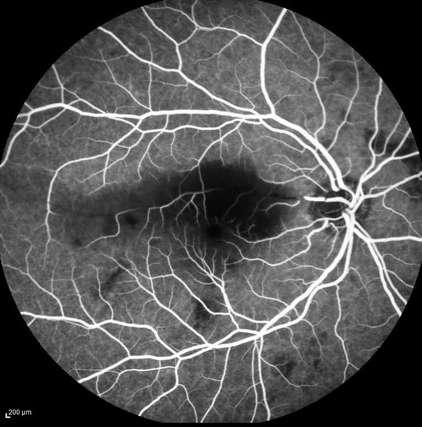

2.D. HERIDA PENETRANTE OCULAR + CUERPO EXTRAÑO INTRAOCULAR

A B

Caso aportado por Dr. Álvaro Rodriguez

Imagen C: üRotura de la capsula anterior (Herida penetrante cristalienana)

Imagen D

üEl cuerpo extraño metalico probablemente golpeó la retina en la parte inferior (donde se ve edema de retina, algo de esclera desnuda y hemorragia)

2.D. HERIDA PENETRANTE

+ CUERPO EXTRAÑO INTRAOCULAR

OCULAR

INTRAOCULAR